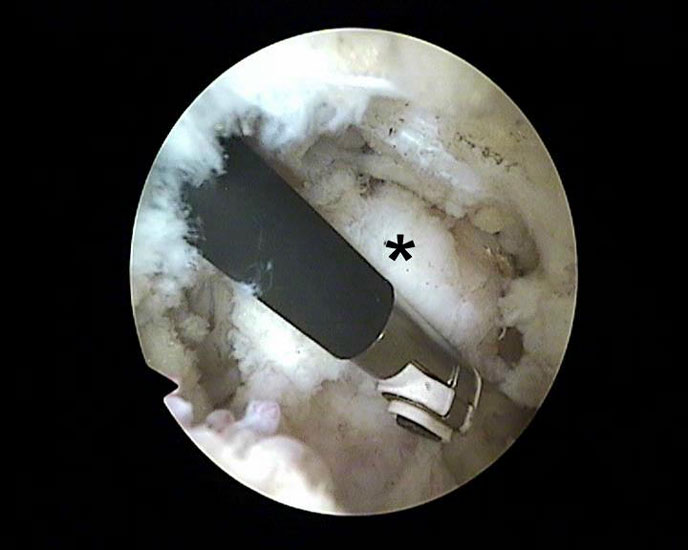

Abbildung Nr. 11-13

Das Os trigonum wird aus dem Weichteilgewebe gelöst und anschließend mit einer Fasszange entfernt. Bei größeren Knochenfragmenten muss ggf. das mediale Arthroskopieportal um wenige Millimeter verlängert werden, um die Extraktion zu ermöglichen. Nach Resektion des Os trigonum ist die posteriore Facette des Subtalargelenks erkennbar (rechte Seite, PF=posteriore Facette, FHL=Flexor hallucis longus-Sehne, T = Talus, K = Kalkaneus, *=Os trigonum).